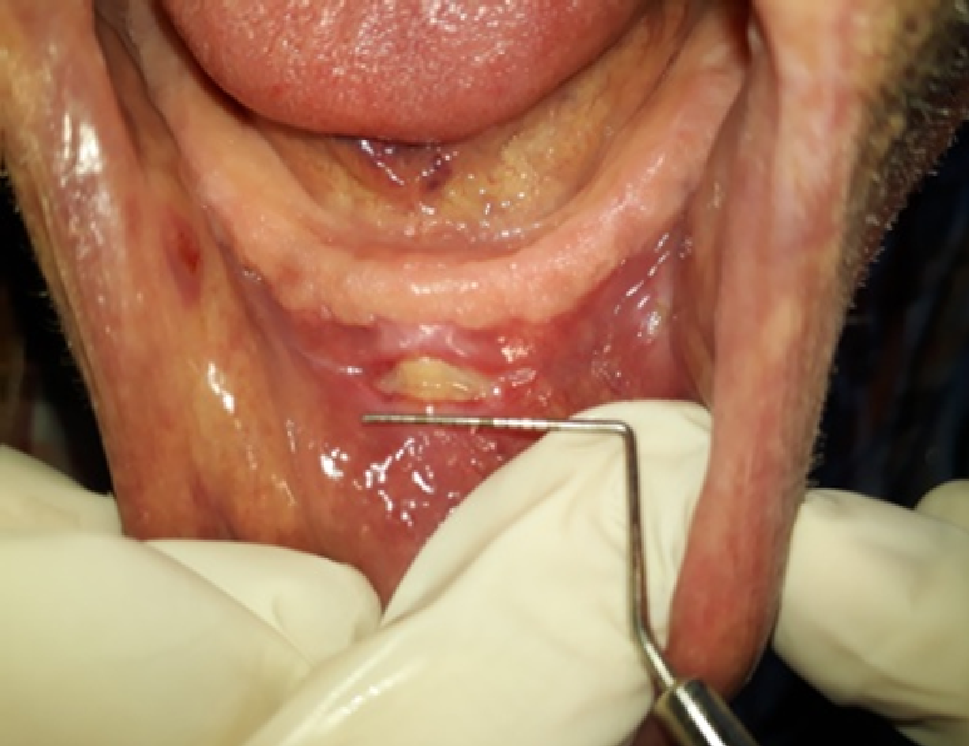

Measuring ulcers with William’s probe.